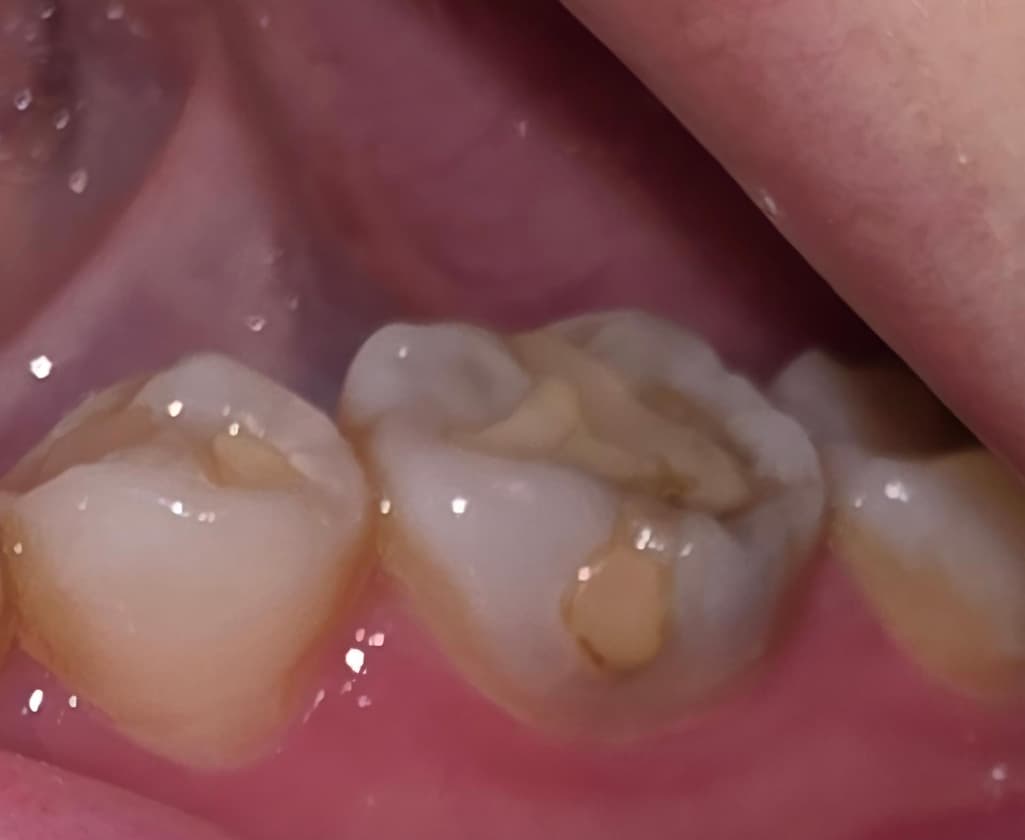

육포를 씹다가 갑자기 왼쪽 아랫부분 어금니가 욱신거리고 너무 아파서 카메라로 보니까 때운 부분이 저렇게 되어있던데 혹시 치아에 금이 간 건가요? ㅠㅠ

떼운부위가 깨져보이고 안쪽으로 충치가 생겼을수도 있고 치아에 금이 갔을수도 있으니 치과에 내원하여 확인하면 좋을것같습니다. 빠른 회복 바라겠습니다. 건강하세요.

떼운 부위가 깨져나갔네요, 사진상으로 봐서 명확하진 않으나 깨져나간 부위 외에도 금이 간 것처럼 보이기도 합니다. 치과 가보시기 바랍니다.

사진으로 봤을 경우에는 이전에 치과용 재료로 충전한 부분 주변에 충치가 생기면서 깨진 것으로 보입니다. 이런 경우 충치치료가 필요할 수 있습니다.

자세한 확인을 위해서 치과에서 진료를 받아보는 것을 권유드립니다.